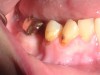

The patient shown in Figure 4 through Figure 6 was a meth user for 6 years. He had a stroke at age 22. After recovering from the stroke and stabilization of his circulatory system was achieved, and once he quit using meth, he strongly desired to apply for a job and wished to improve his dental appearance. He opted to have all of his teeth extracted, as complete dentures were his only treatment option because there were no adequate abutment teeth remaining for placement of removable partial dentures.

Fig 4 through Fig 6. Patient’s oral condition after 6 years of meth use.

Figure 4

Figure 5

Figure 6